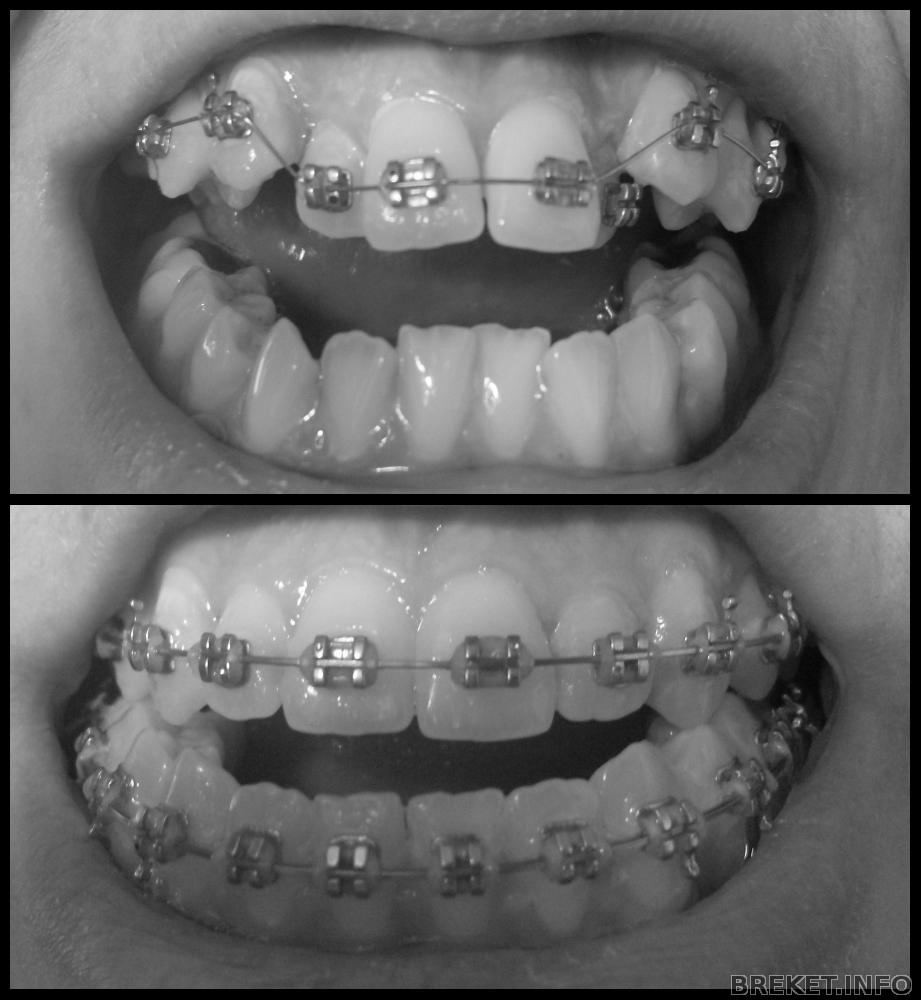

Бываю тут редко, но метко, решила оставить на память запись о том, что уже прошло 5 месяцев с момента как я стала счастливым обладателем БС.

Что могу сказать, время летит незаметно, вроде было всего ничего, вспоминаешь как прошла неделя, месяц, 3 месяца, а на очереди уже и 5 месяц, это не может не радовать, ну буду кратка.. итак: Читать далее »